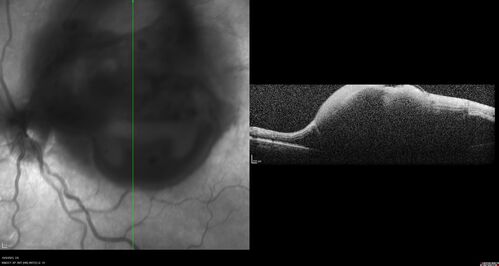

Ruptured Retinal Arterial Macroaneurysm - Submacular hemorrhage and BRAO

81 year old female with vision loss for a few days. Coumadin was high with INR at 3.1 VA 6/200